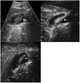

Gallbladder polyp

Gallbladder polyps are growths or lesions resembling growths (polypoid lesions) in the wall of the gallbladder. True polyps are abnormal accumulations of mucous membrane tissue that would normally be shed by the body. [Source: Wikipedia ]